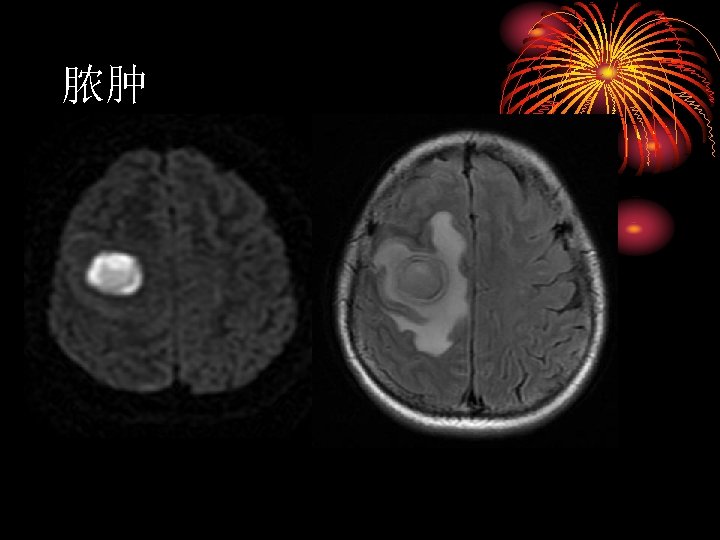

The mass has well defined borders and partially effaces the atrium (trigone) of the left lateral ventricle. There is mild patchy enhancement. DWI images demonstrate increased signal throughout, but only the even more hyperintense rim demonstrates true restricted diffusion on ADC images. The remainder of the mass is increased signal on ADC images, indicating increased diffusivitiy.